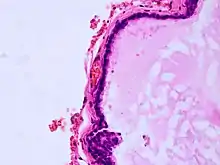

Histopathology of colloid cyst